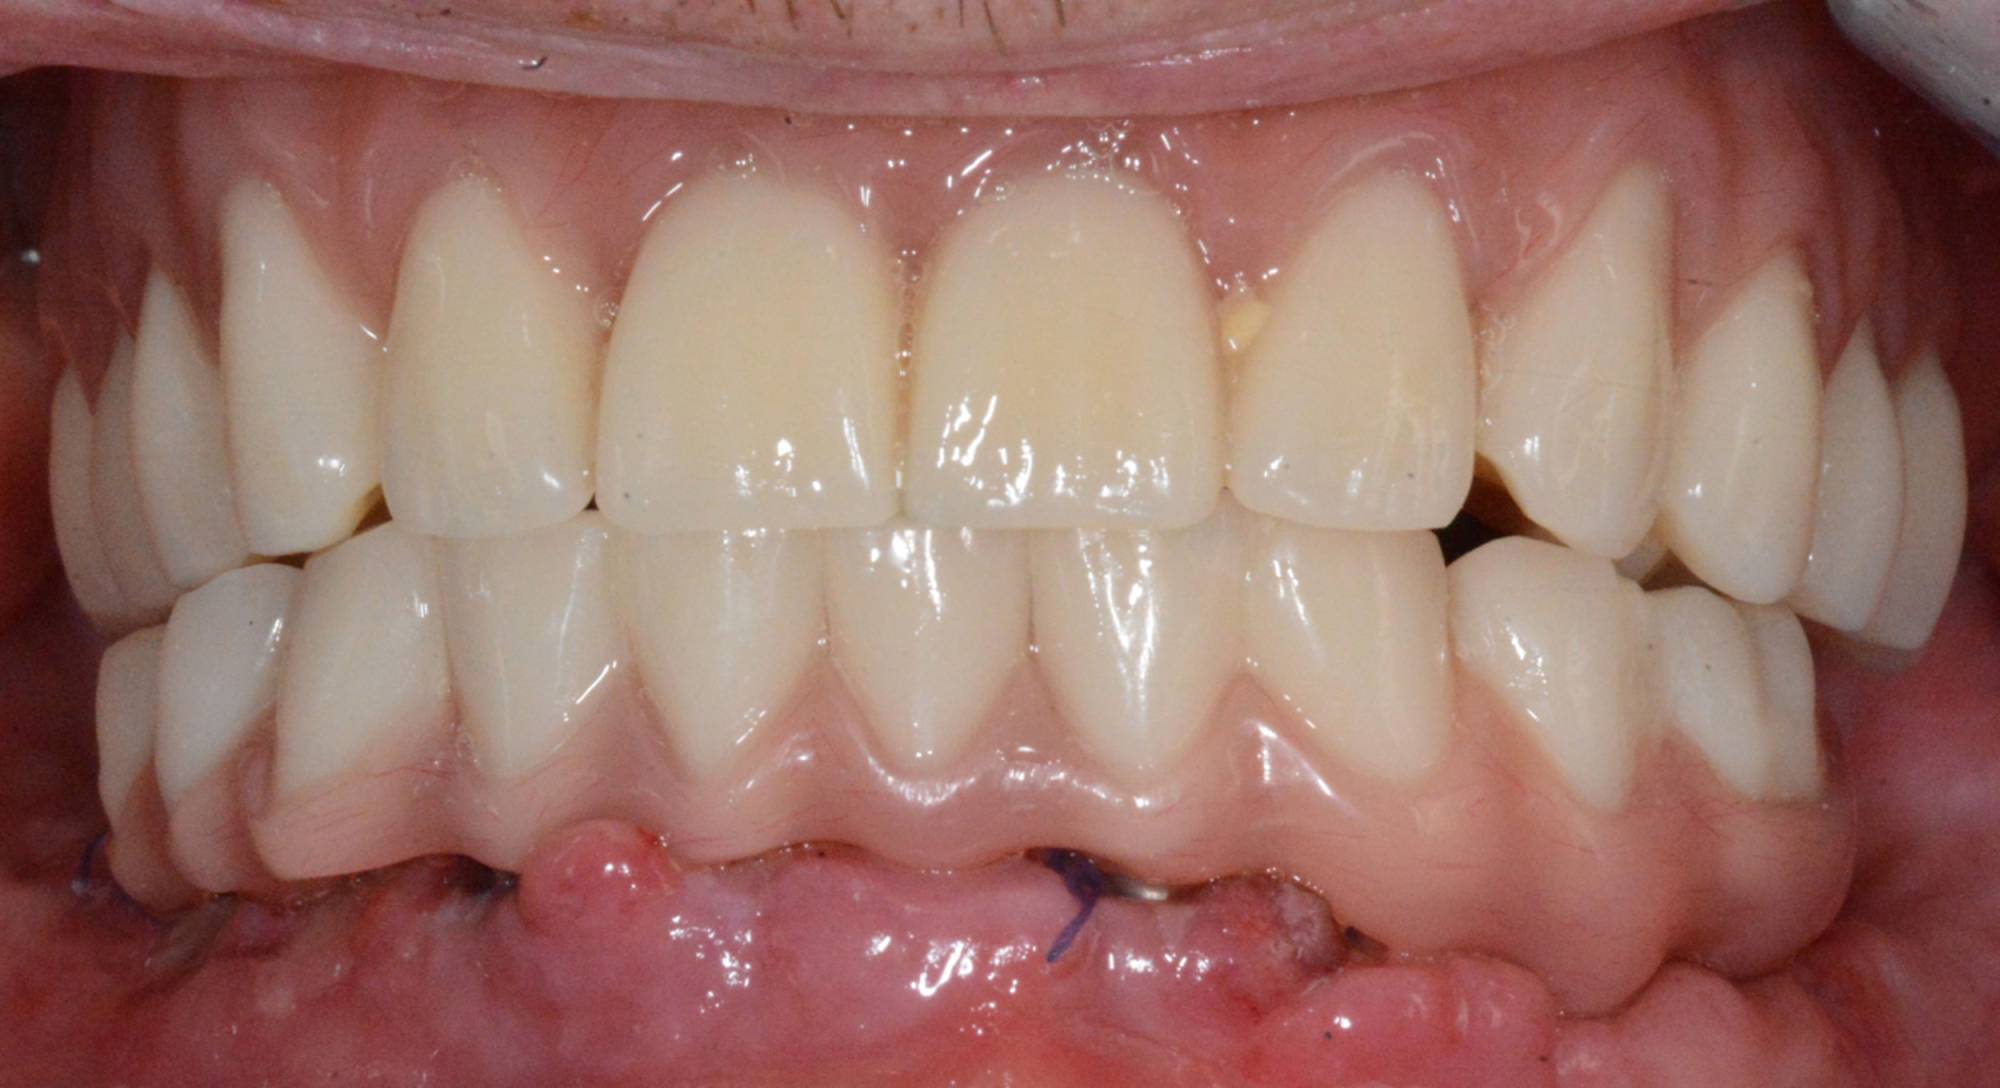

Tuttavia, in alcuni casi selezionati, è possibile protesizzare gli impianti subito dopo il loro posizionamento, nel giro di pochi giorni o addirittura nel corso della stessa seduta: questa tecnica è definita “carico immediato” e consente al paziente di entrare in Studio con la sua vecchia dentiera e di uscire il giorno stesso con una protesi fissa.